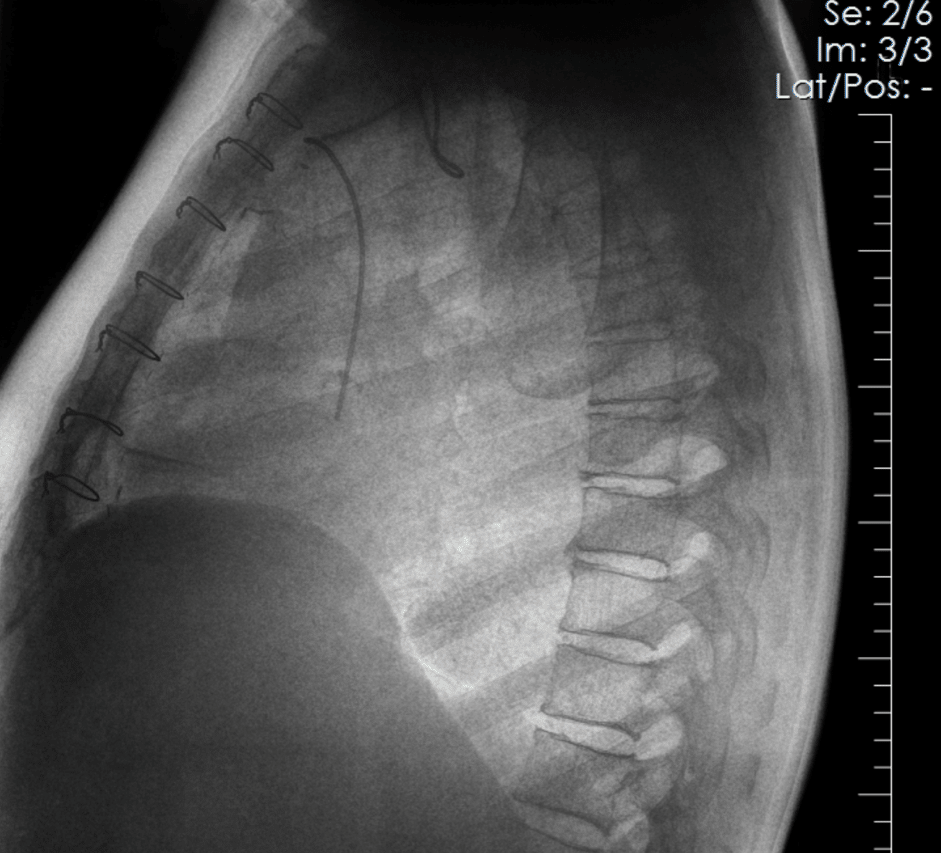

Coronary artery calcium becomes visible in the SpectralDR bone image and is confirmed on CT.

SpectralDR bone images emphasize skeletal structures, allowing clearer visualization of the fracture compared with the conventional radiograph.